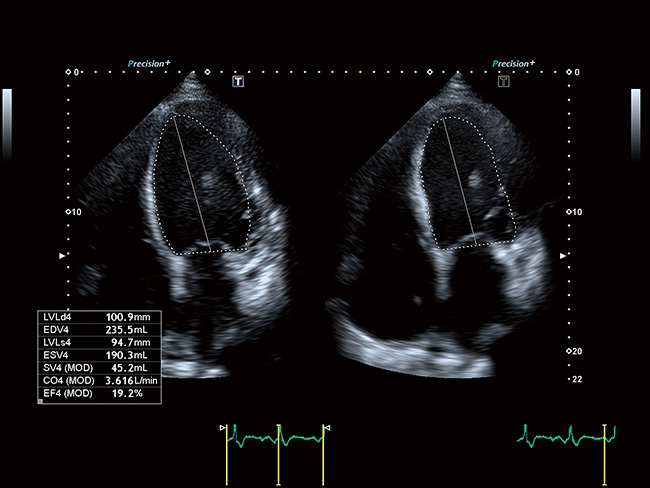

Отличная цветопередача с высокой детализацией и четкостью изображения. Устройство подходит для профессионального использования в частных кабинетах и крупных медицинских центрах. Комплектация сканера применима для самых разных исследований. Широкий диапазон прикладного клинического программного обеспечения высокоэффективен для общих исследований, сердечно-сосудистых, гинекологических, ортопедических, урологических.

Aplio a550 может работать с линейным матричным датчиком и поддерживает новейшие монокристаллические датчики. Также Aplio a550 поддерживает большое количество дополнительных опций, таких как - SMI, Компрессионная эластография, Эластография сдвижной волны, Smart Fusion, исследования с использованием контраста (CEUS), 3D реконструкции в реальном времени (4D), функции автоматической оценки подвижности миокарда и фракции выброса.

Кардиология:

Да

Стресс-эхо:

TDI: